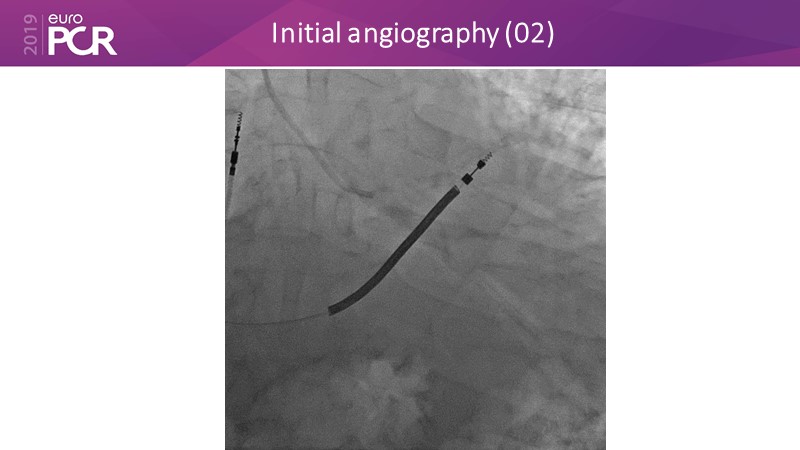

Distal left main stenosis: how to treat optimally with dedicated bifurcation stent BiOSS Lim C. Case-based session

Consult this session to learn more about the multiple technological options with dedicated bifurcation stent for complex left main bifurcation lesions, and the applicability of this stent for the different clinical presentations.